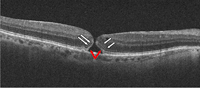

En formas recientes de agujero macular puede verse conservación de la capa elipsoide y de la membrana limitante interna en los bordes del agujero (

Figura 7). En formas con una mayor cronicidad suele perderse la integridad de la capa elipsoide y de la membrana limitante externa, aparece un levantamiento de los bordes con un edema quístico en los márgenes del agujero y se aprecian alteraciones del epitelio pigmentario (

Figura 8).

Figura 7. Agujero macular de reciente aparición. Se objetiva un defecto completo de todas las capas de la retina. Es posible apreciar con claridad la membrana limitante interna (flechas blancas) y la capa elipsoide (flechas rojas) en los márgenes del agujero.

Figura 8. Agujero macular crónico. Se aprecia un levantamiento de los bordes del agujero, con edema quístico. En los márgenes del agujero no pueden diferenciarse la membrana limitante interna y la capa elipsoide.